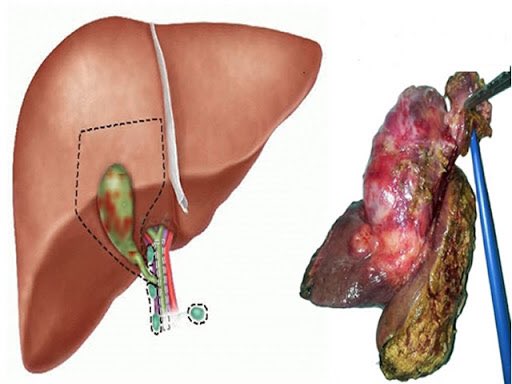

Your pancreas sits deep in the abdomen and has two main jobs:

• Producing digestive enzymes that help break down food

• Releasing hormones like insulin that control blood sugar

When fat accumulates inside this organ, it can interfere with both. Doctors often find fatty pancreas together with fatty liver, since both conditions share common risk factors.